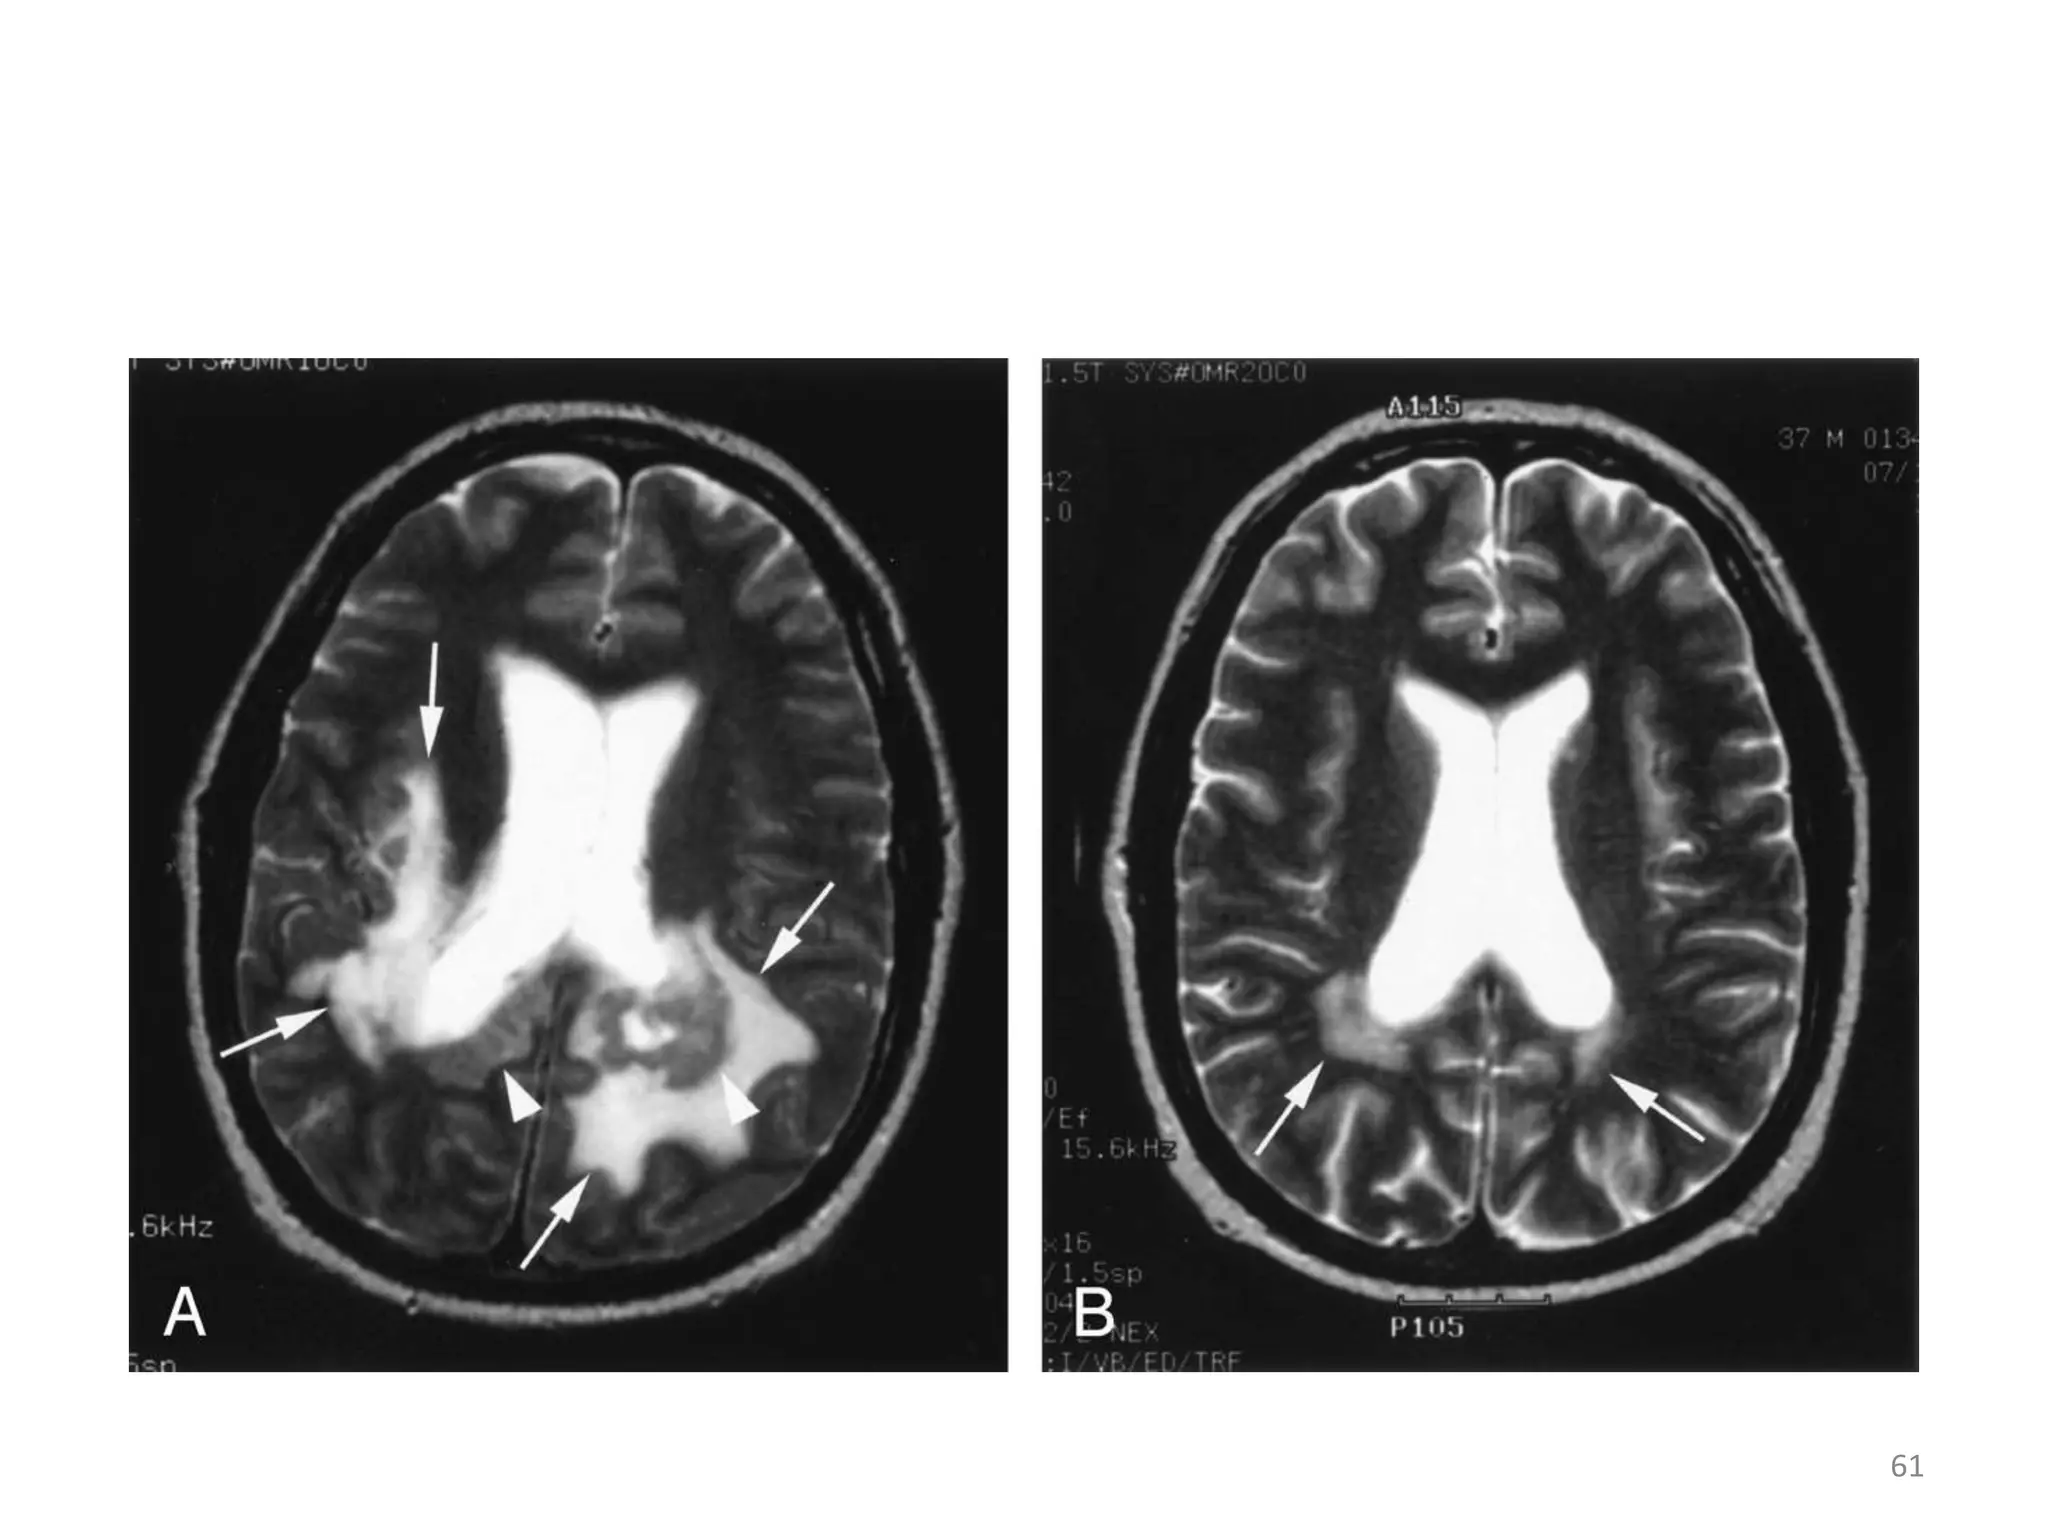

PROGRESSIVE MULTOFOCAL LEUCOENCEPHALOPATHY

• Demyelinating disease caused by papavavirus.

• Occurs at very low cd4+ counts

• Presents with hemiperesis, visual/speech defects,

altered mood,ataxia and seizures.

• Diagnosis by MRI, viral particle detection in the CSF.

PRIMARY CNS LYMPHOMA:

• These are high grade ,diffuse, B- cell lymphomas

which occur in late stage HIV .

• History is 2-8 weeks of headaches focal features

and sometimes confusion; seizures occur in 15%

but fever is absent.

• Imaging demonstrates a large, single,

homogeneously enhancing periventricular lesion

with mild to moderate surrounding oedema and

mass effect.

• Biopsy is definitive, but carries a small risk of

morbidity.

PROGRESSIVE MULTOFOCAL LEUCOENCEPHALOPATHY • Demyelinating disease caused by papavavirus. • Occurs at very low cd4+ counts • Presents with hemiperesis, visual/speech defects, altered mood,ataxia and seizures. • Diagnosis by MRI, viral particle detection in the CSF. 59

• 60.

PRIMARY CNS LYMPHOMA: • These are high grade ,diffuse, B- cell lymphomas which occur in late stage HIV . • History is 2-8 weeks of headaches focal features and sometimes confusion; seizures occur in 15% but fever is absent. • Imaging demonstrates a large, single, homogeneously enhancing periventricular lesion with mild to moderate surrounding oedema and mass effect. • Biopsy is definitive, but carries a small risk of morbidity. 60